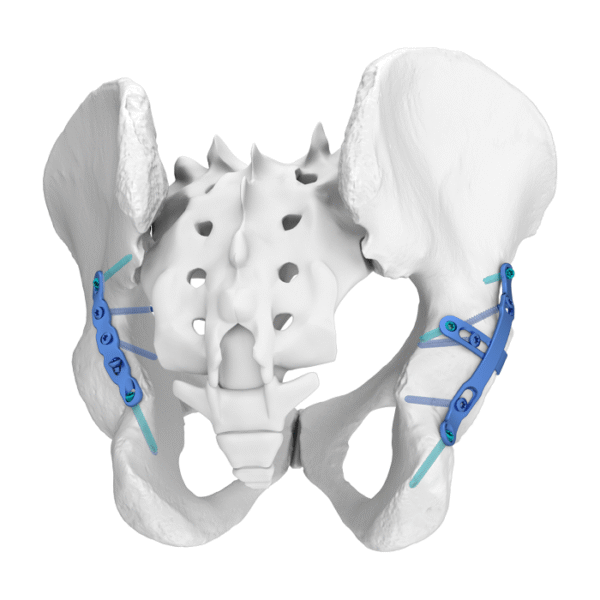

– El diseño curvo asegura una compresión efectiva del borde de fractura.

– El borde afilado permite la compresión directa del hueso a través de la cápsula articular.

– El primer orificio está diseñado como un orificio alargado, conveniente para elegir la posición del tornillo.

– Fracturas de la pared posterior del acetábulo.